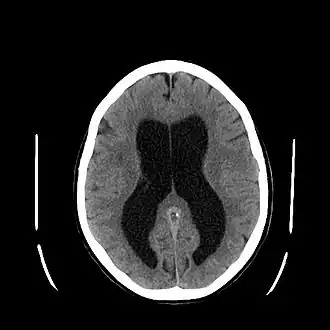

Hydrocéphalie

L’hydrocéphalie (du grec ancien ὕδωρ / húdôr (« eau ») et κεφαλή / kephalế (« tête »)) est une anomalie neurologique sévère, définie par l'augmentation du volume des espaces contenant le liquide cérébrospinal (LCS) : ventricules cérébraux et espace subarachnoïdien. Cette dilatation peut être due à une hypersécrétion de LCS, un défaut de résorption, ou une obstruction mécanique des voies de circulation. Dans les familles issues de mariages entre apparentés, l'enfant consanguin a 13 fois plus de risques de développer une hydrocéphalie[1].

- Le scanner cérébral (sans injection d'iode) retrouve une dilatation quadriventriculaire sans élargissement des sillons corticaux sur l'ensemble de la convexité corticale et un arrondissement des angles latéraux des ventricules (ce qui permet de différencier hydrocéphalie et atrophie cérébrale).

- L'IRM cranioencéphalique est devenu l'examen de référence. Il permet de mettre en évidence la dilatation des ventricules et des anomalies périventriculaires